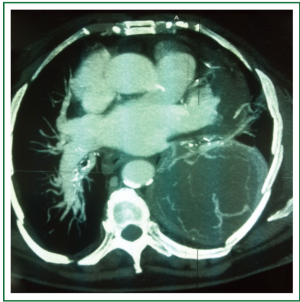

An 81-year-old woman was admitted to hospital for investigations after complaining of left chest pain. She and her family had no specific history and she was no smoker. Patient presented with a chest pain. The chest roentgenogram revealed a nodular shadow within the left lung. A subsequent chest computed tomography (CT) showed a 10 cm × 9 cm, well-circumscribed, intrapulmonary nodular lesion with a large basal pleural connection in the postero-basal and lateral-basal wall of left lung (Figure 1).

There was no mediastinohilar lymphadenopathy or secondary lesions. Other findings were normal.